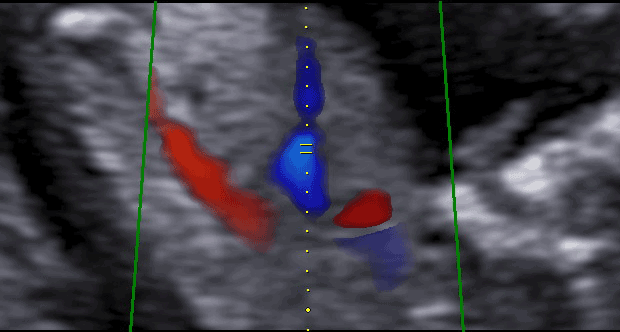

Agenesia de Ducto Venoso

Vídeo cortesia do Dr. Jader Cruz – The Fetal Medicine Foundation Agenesia de Ducto Venoso O ducto…